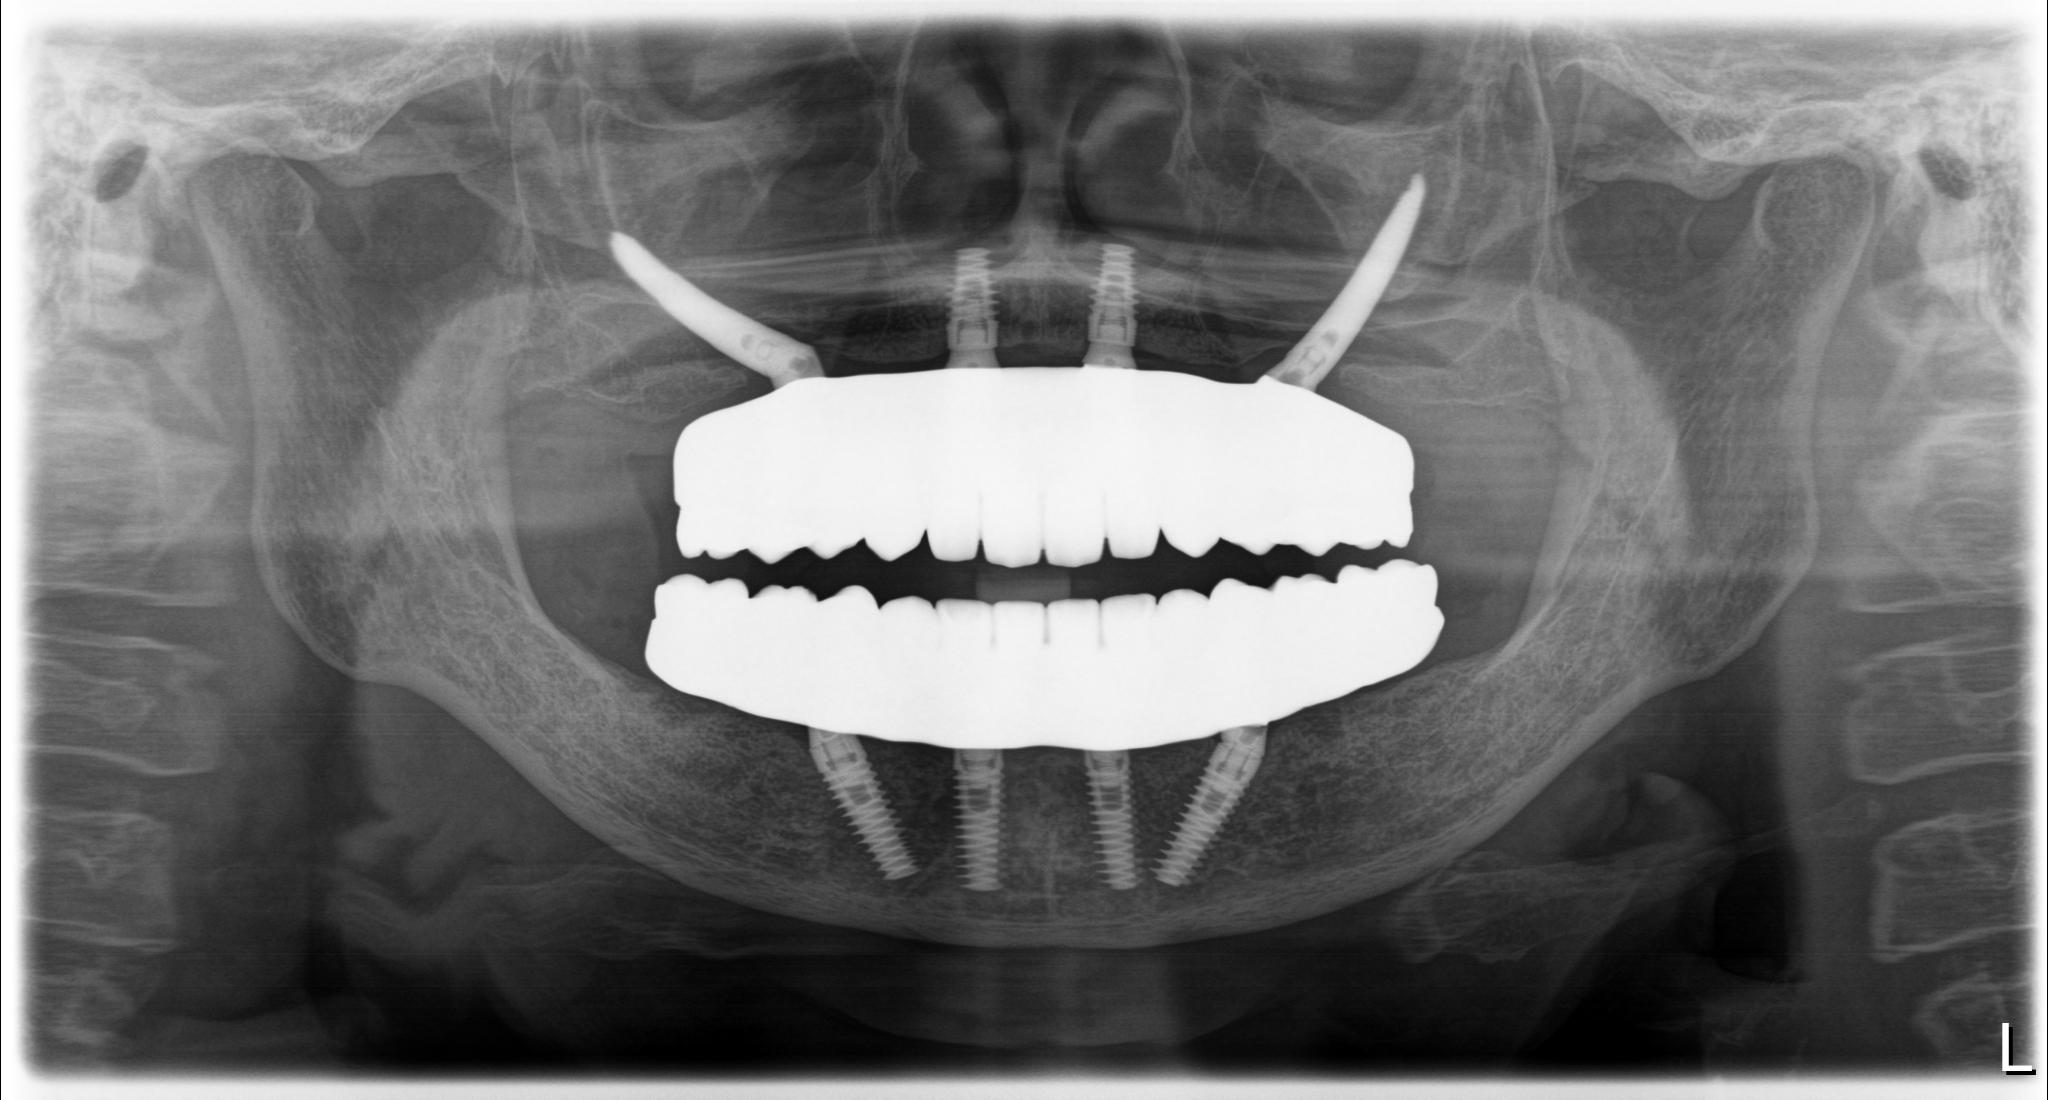

内容 :上下顎オールオン4ザイゴマ2

費用 :5,552,800円

※モニター価格

期間 :半年

リスク:出血・腫れ・痺れ・痛み